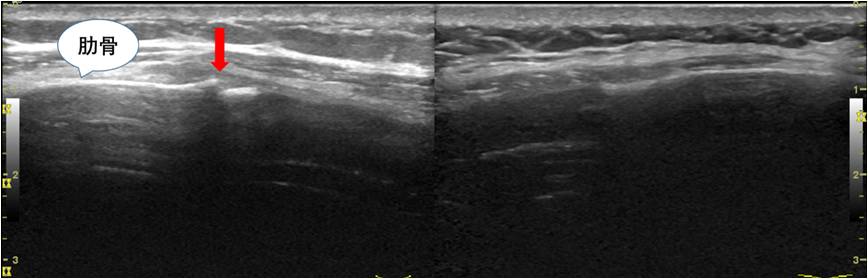

小王抱着试一试的态度来到了北医三院超声科肌骨超声门诊,超声医师接诊后根据小王描述的疼痛症状,对可疑肋骨区域进行仔细的扫查,发现了引起小王持续胸部疼痛的病因:的确是肋骨骨折了,而且很明确的告知他是右侧第七前肋骨折,因骨折端对位良好,不需特殊治疗,可适当使用外敷药物缓解疼痛症状,同时不宜再做剧烈运动。三个月后患者再次超声复查,发现肋骨骨折端已完全愈合。

患侧 对侧(正常侧)